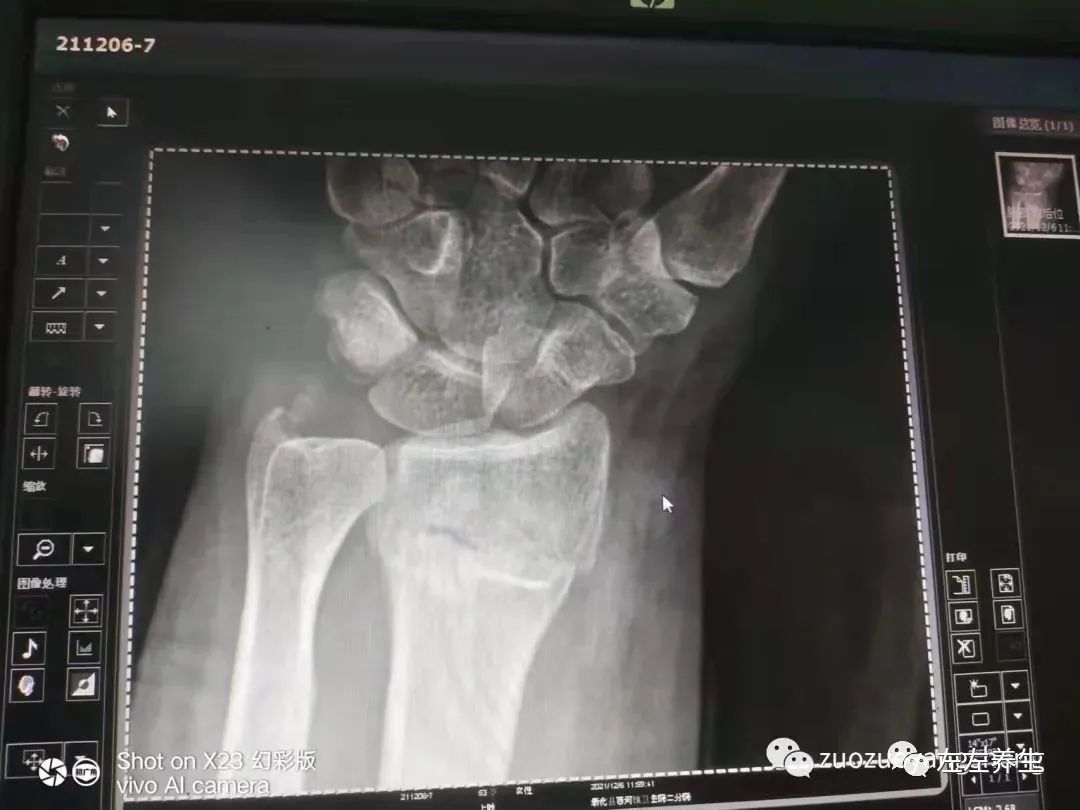

2021年12月6日,爱人给头晕的同事按推后,想去食堂弄点姜汤给她喝,因走的急没有注意到食堂地面上已撒了搞卫生的洗洁精,脚一滑,身体被重重的摔出了几米。等她爬起来时,发现左手手腕剧痛且动弹不得。怀疑是骨折,于是赶紧陪同爱人去医院照片。结果,手腕处桡骨呈一字形,整齐断裂,且明显错位。

附CT: